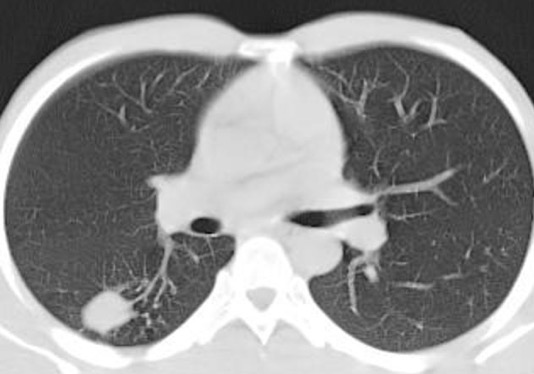

CT pulmonary angiography shows significant partial filling defects involving the right and left pulmonary artery with extension to its lobar branches. Main pulmonary artery to aorta ratio is increased (greater than 1).

Case courtesy of Dr Jeremy Jones, <ahref=”https://radiopaedia.org/”>Radiopaedia.org</a>. From the case <a href=”https://radiopaedia.org/cases/13211″>rID: 13211</a>

The other imaging findings to be mentioned (as they indicate prognosis) are:

- Thrombus burden (subjective)

- Right ventricle: Left ventricle ratio (normal<0.9)

- Changes in bilateral lungs (infarcts)

- Contrast reflux into IVC (due to high pressure in the right atrium).

The most important poor prognostic indicator is increased RV/LV ratio which is a sign RV strain.